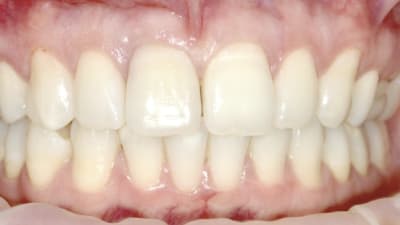

Oral Health Insights Periodontics Oral Surgery Enhancing Esthetic Outcomes Through Periodontal Plastic Surgery By P.D. Miller, DDS, Peter Nordland, DMD, Robert A. Levine, DDSDDS March 01, 2018 4 min read